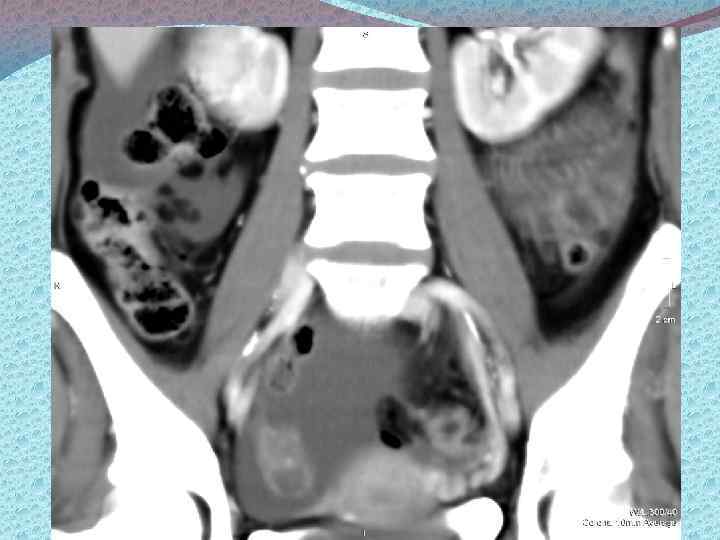

Методы диагностики: Визуализирующие: а)лучевые б)эндоскопические Лучевые: УЗИ, КТ, МРТ. Эндоскопические: лапароскопия, пункция заднего свода, забор материала для гистологического исследования. Лабораторные. Определение типов опухолевых маркеров: 1) онкофетальные и онкоплацентарные а/г (РЭА, АФП ХГЧ, ТБГ) 2) Опухолеассоциированные антигены (СА 125, СА 19 9, СА 72 4) 3) Ферменты (ПЩФ, НСЕ) 4) Гормоны (кальцитонин, эстрадиол, пролактин, ТТГ) 5) Продукты онкогенов 6) Белки острой фазы (ферритин, С реактивный белок, РЭА) 7) Биологически активные пептиды (ПГ, ГАГ, M CSF)

Стадирование злокачественных опухолей яичников: Первый этап: Физикальные методы обследования, в том числе осмотр шейки матки зеркалами; Са 125 в крови и моче; УЗИ органов брюшной полости, таза; Цитологическое исследование пунктата заднего свода влагалища Второй этап (для более точной оценки распространенности процесса, наличия метастазов): Компьютерная и магниторезонансная томография Рентгенография органов грудной клетки Цистоскопия, Внутривенная урография Сцинтография костей скелета